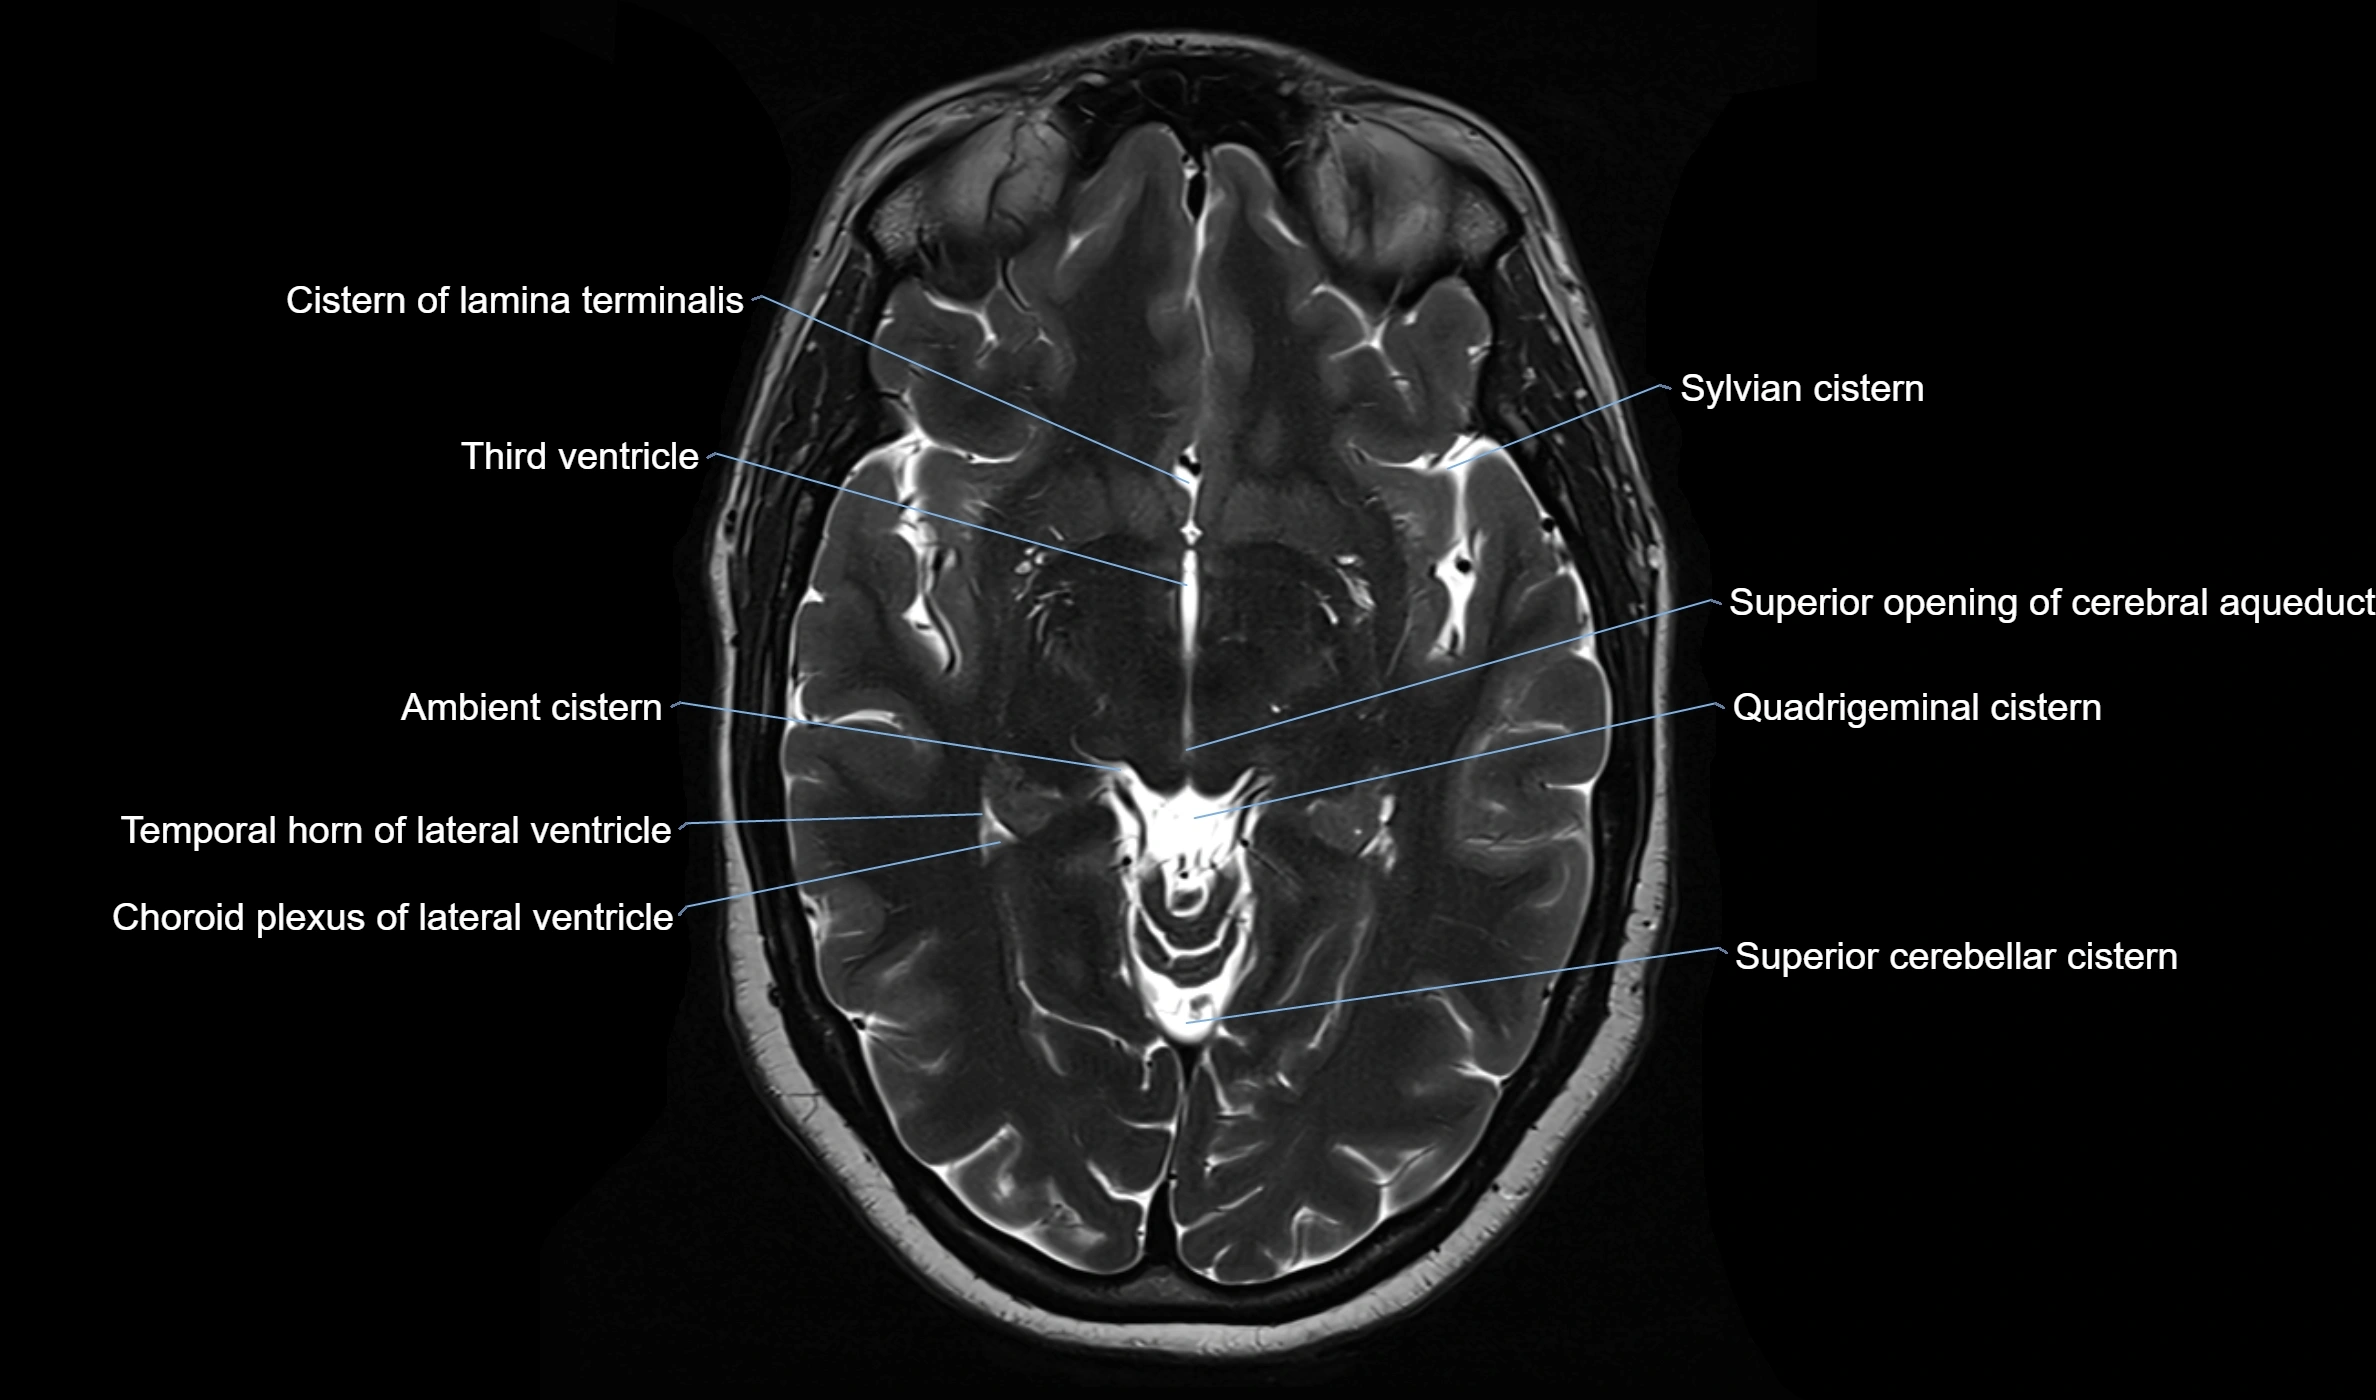

MRI images

image